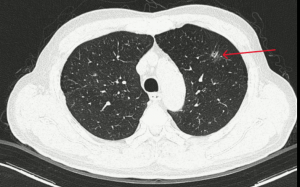

Trong quá trình điều trị sỏi thận, một bệnh nhân 69 tuổi bất ngờ được phát hiện ung thư phổi giai đoạn rất sớm nhờ hệ thống phân tích hình ảnh bằng trí tuệ nhân tạo (AI).